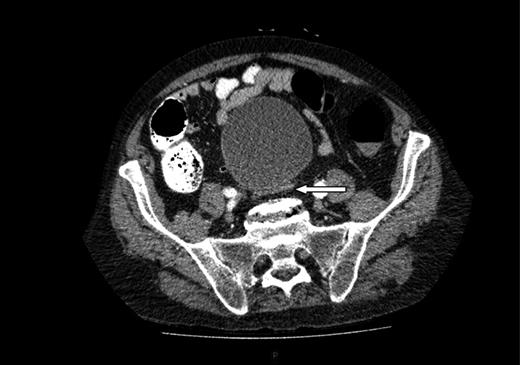

A computed tomography (CT) of the abdomen and pelvis was performed. This showed a grossly distended urinary bladder and compression of the sigmoid colon against the sacral promontory causing bowel obstruction (Figs 1 and 2, respectively) as well as a 4.9 cm abdominal aortic aneurysm without any signs of a rupture (Fig. 3). The plan was to consult our vascular colleagues regarding management of the AAA once the obstruction had settled.

The initial CT scan of the abdomen showing a large distended bladder.